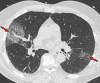

Chest CT has a potential role in the diagnosis, detection of complications, and prognostication of coronavirus disease 2019 (COVID-19). Implementation of appropriate precautionary safety measures, chest CT protocol optimization, and a standardized reporting system based on the pulmonary findings in this disease will enhance the clinical utility of chest CT. However, chest CT examinations may lead to both false-negative and false-positive results. Furthermore, the added value of chest CT in diagnostic decision making is dependent on several dynamic variables, most notably available resources (real-time reverse transcription-polymerase chain reaction [RT-PCR] tests, personal protective equipment, CT scanners, hospital and radiology personnel availability, and isolation room capacity) and the prevalence of both COVID-19 and other diseases with overlapping manifestations at chest CT. Chest CT is valuable to detect both alternative diagnoses and complications of COVID-19 (acute respiratory distress syndrome, pulmonary embolism, and heart failure), while its role for prognostication requires further investigation. The authors describe imaging and managing care of patients with COVID-19, with topics including (a) chest CT protocol, (b) chest CT findings of COVID-19 and its complications, (c) the diagnostic accuracy of chest CT and its role in diagnostic decision making and prognostication, and (d) reporting and communicating chest CT findings. The authors also review other specific topics, including the pathophysiology and clinical manifestations of COVID-19, the World Health Organization case definition, the value of performing RT-PCR tests, and the radiology department and personnel impact related to performing chest CT in COVID-19. ©RSNA, 2020.